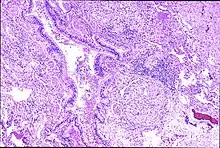

Peribronchal non-necrotizing granuloma from berylliosis | |

Granulomas are seen in other chronic diseases, such as tuberculosis and sarcoidosis, and it can occasionally be hard to distinguish berylliosis from these disorders. However, granulomas of chronic beryllium disease will typically be non-caseating, i.e. not characterized by necrosis and therefore not exhibiting a cheese-like appearance grossly.[5]